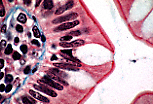

单层柱状被覆上皮(回肠)

单层柱状被覆上皮分布于回肠(小肠的一部分)。

小肠在食糜消化和消化产物营养吸收中发挥关键作用。为实现吸收功能,小肠与食糜接触的表面积通过多种结构被显著扩大:小肠的长度(肠袢)、黏膜皱襞、肠绒毛和微绒毛。 |

从图像中央的肠腔开始,回肠壁可识别出以下区域:黏膜皱襞区、结缔组织区(黏膜下层)、平滑肌组织区(肌层)。 |

该回肠壁切片中可见黏膜皱襞。

皱襞上突出的指状突起即为肠绒毛。 |

肠绒毛由中央结缔组织轴心和表面覆盖的肠上皮构成。绒毛之间可见 利贝昆氏腺(肠腺) 的开口。 |